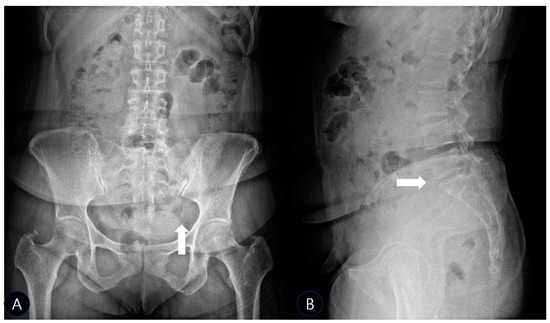

Background: Deep gluteal syndrome (DGS) is an underdiagnosed cause of sciatica-like pain, involving the entrapment of the sciatic nerve by various structures within the subgluteal space. While cases of ossification or calcification in the context of severe pelvic imbalance have been rarely reported, isolated SSL calcification as a primary cause of DGS remains largely unexplored and undocumented. This case report presents the first documented instance of sacrospinous ligament (SSL) calcification identified as the primary cause of DGS and its successful management with ultrasound-guided prolotherapy. Case Presentation: A 51-year-old female presented with severe, worsening left-sided sciatica of several months’ duration. Physical examination revealed an antalgic gait, positive sacroiliac joint tests, and multiple positive DGS-specific provocative tests (FAIR, Pace sign, Seated Piriformis Stretch). Radiographs and musculoskeletal ultrasound (MSK-US) confirmed calcification within the left sacrospinous ligament, with associated sciatic nerve swelling. The patient underwent three sessions of ultrasound-guided prolotherapy (dextrose 10% with lidocaine) targeting the calcification site, followed by a structured rehabilitation program. Results: The patient reported a significant reduction in pain, from a Visual Analog Scale (VAS) score of 10/10 to 1/10 within one month. All previously positive provocative tests converted to negative, indicating a resolution of the nerve entrapment. Functional mobility was fully restored. Conclusions: This case highlights isolated sacrospinous ligament calcification as a potential and previously overlooked pathological entity responsible for deep gluteal syndrome. To our knowledge, this is the first report to implicate ligamentous calcification as a primary etiological factor in DGS. Musculoskeletal ultrasound proved indispensable for both diagnosis and treatment guidance. Furthermore, ultrasound-guided prolotherapy emerged as a successful and minimally invasive therapeutic option in this case, potentially by stabilizing the ligament and reducing neurogenic inflammation. This case expands the differential diagnosis of sciatica, introduces a new target for intervention in refractory cases, and underscores the need for future studies in larger patient cohorts to validate these findings. Full article

Figure 1